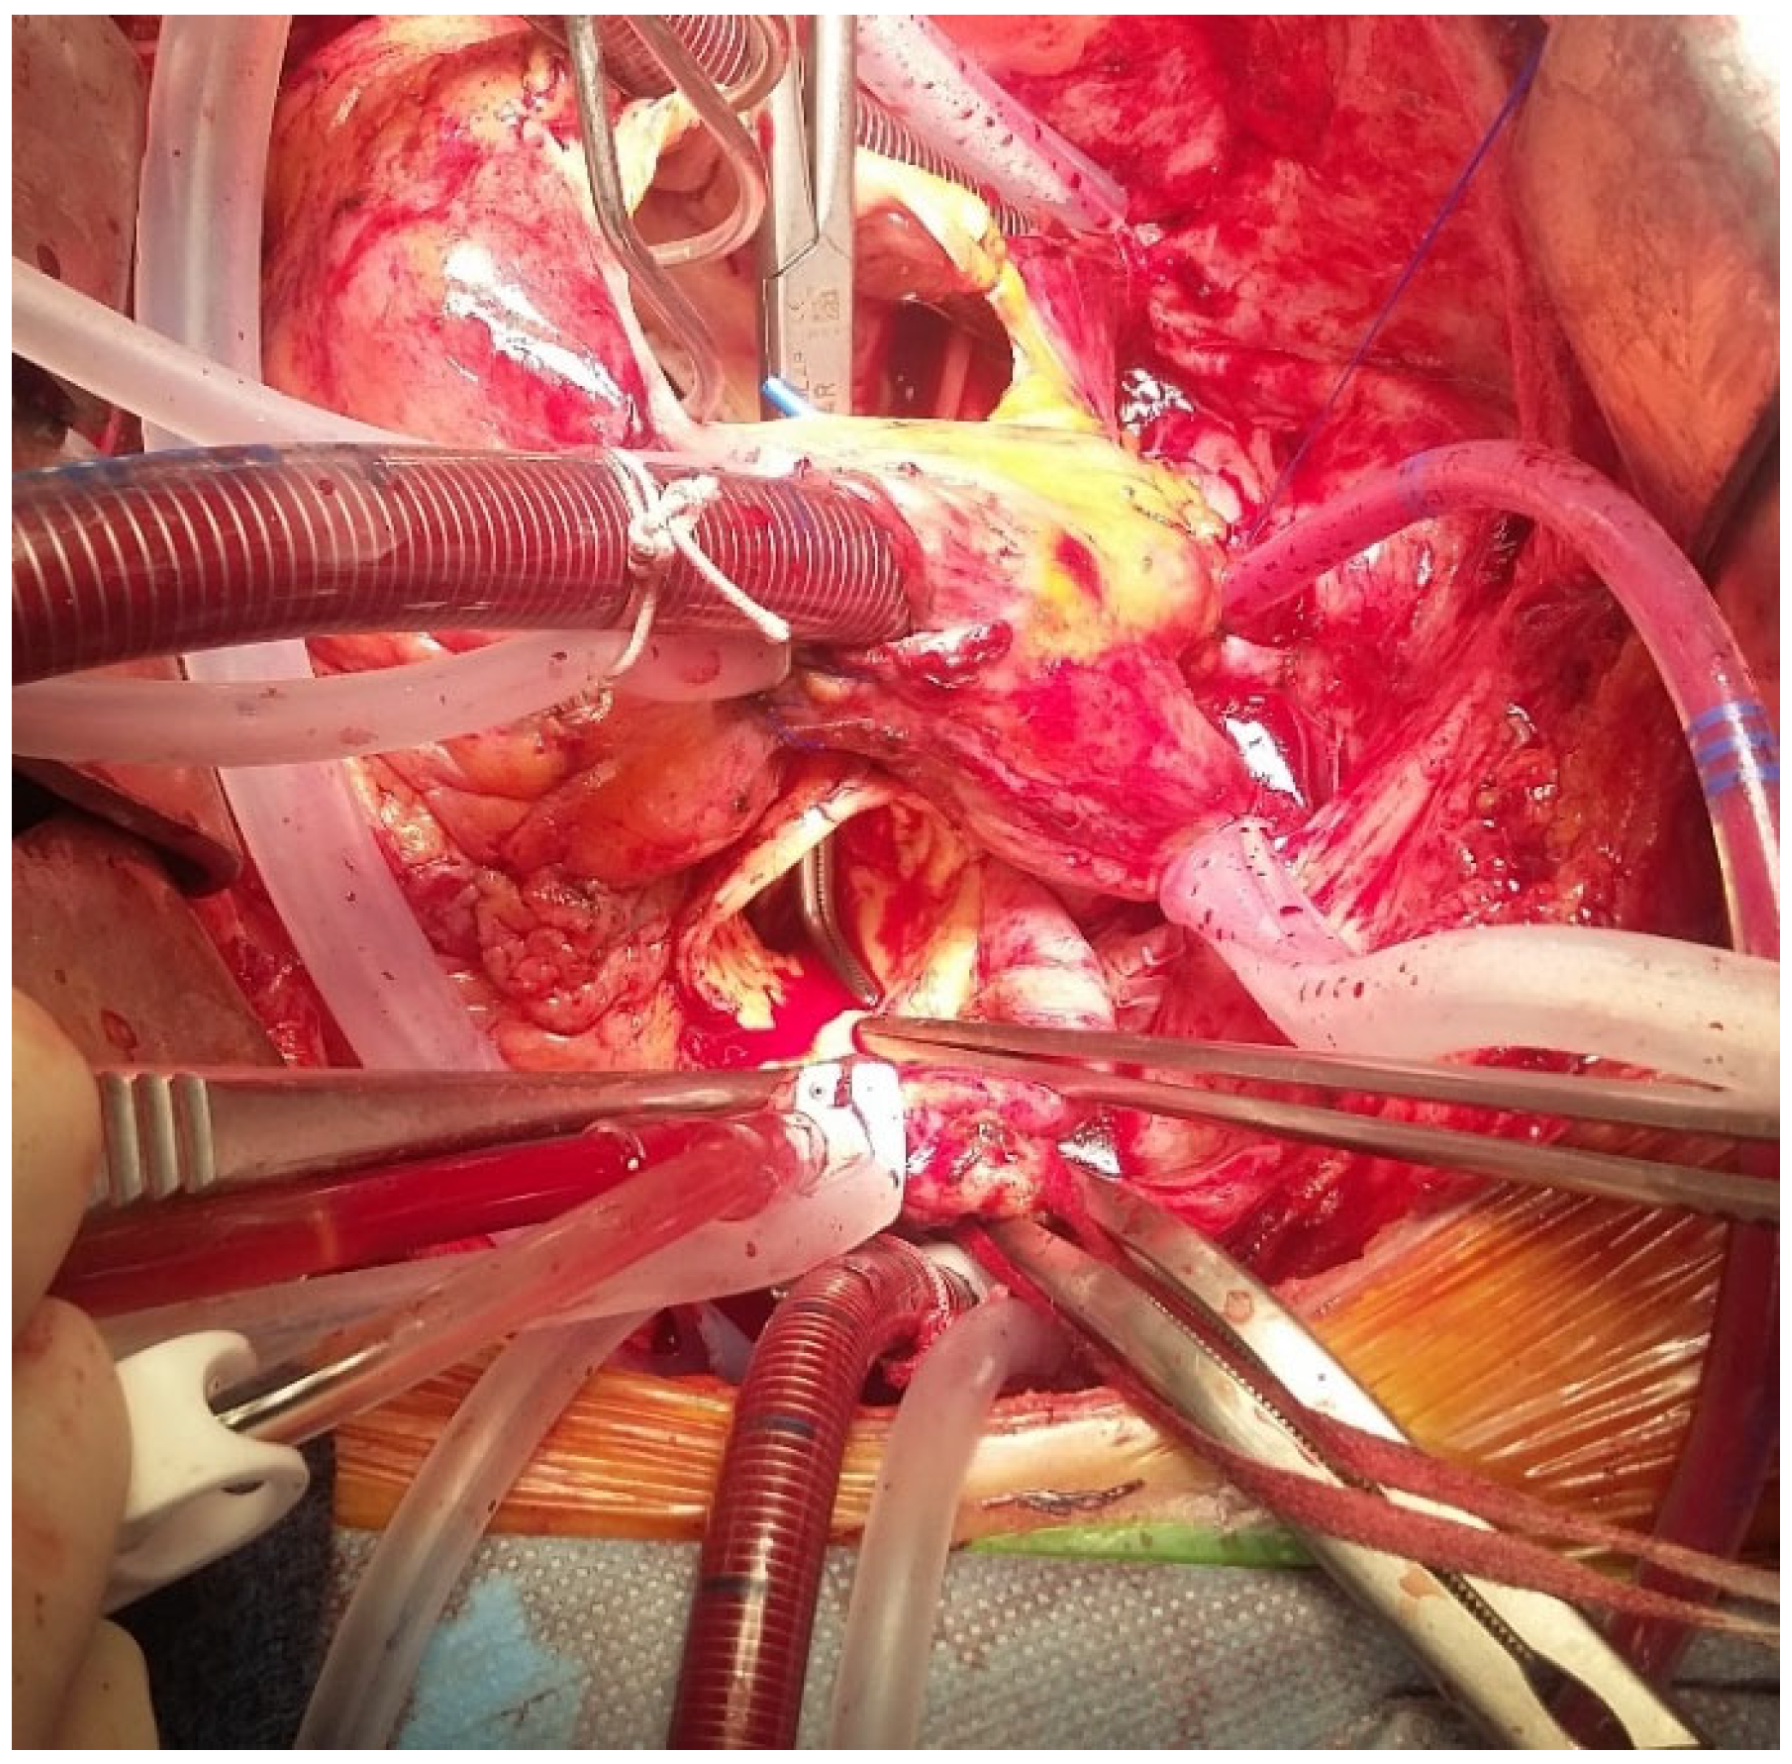

Figure 5 and Figure 6 show an explanted Perceval valve and intraoperative findings of endocarditis involving a Perceval valve.

Figure 6. Aortic to right atrium fistula (highlighted by the path of the dissector) in a case of endocarditis on a Perceval prosthesis.